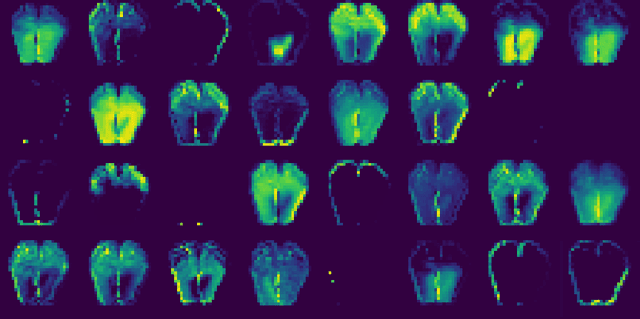

Abstract:Background: In the absence of prospective data on diabetic foot ulcers (DFU), cross-sectional associations with causal risk factors (peripheral neuropathy, and peripheral arterial disease (PAD)) could be used to establish the validity of plantar thermography for DFU risk stratification. Methods: First, we investigated the associations between the intrinsic clusters of plantar thermographic images with several DFU risk factors using an unsupervised deep-learning framework. We then studied associations between obtained thermography clusters and DFU risk factors. Second, to identify those associations with predictive power, we used supervised learning to train Convolutional Neural Network (CNN) regression/classification models that predicted the risk factor based on the thermograph (and visual) input. Findings: Our dataset comprised 282 thermographs from type 2 diabetes mellitus patients (aged 56.31 +- 9.18 years, 51.42 % males). On clustering, we found two overlapping clusters (silhouette score = 0.10, indicating weak separation). There was strong evidence for associations between assigned clusters and several factors related to diabetic foot ulceration such as peripheral neuropathy, PAD, number of diabetes complications, and composite DFU risk prediction scores such as Martins-Mendes, PODUS-2020, and SIGN. However, models predicting said risk factors had poor performances. Interpretation: The strong associations between intrinsic thermography clusters and several DFU risk factors support the validity of using thermography for characterising DFU risk. However, obtained associations did not prove to be predictive, likely due to, spectrum bias, or because thermography and classical risk factors characterise incompletely overlapping portions of the DFU risk construct. Our findings highlight the challenges in standardising ground truths when defining novel digital biomarkers.